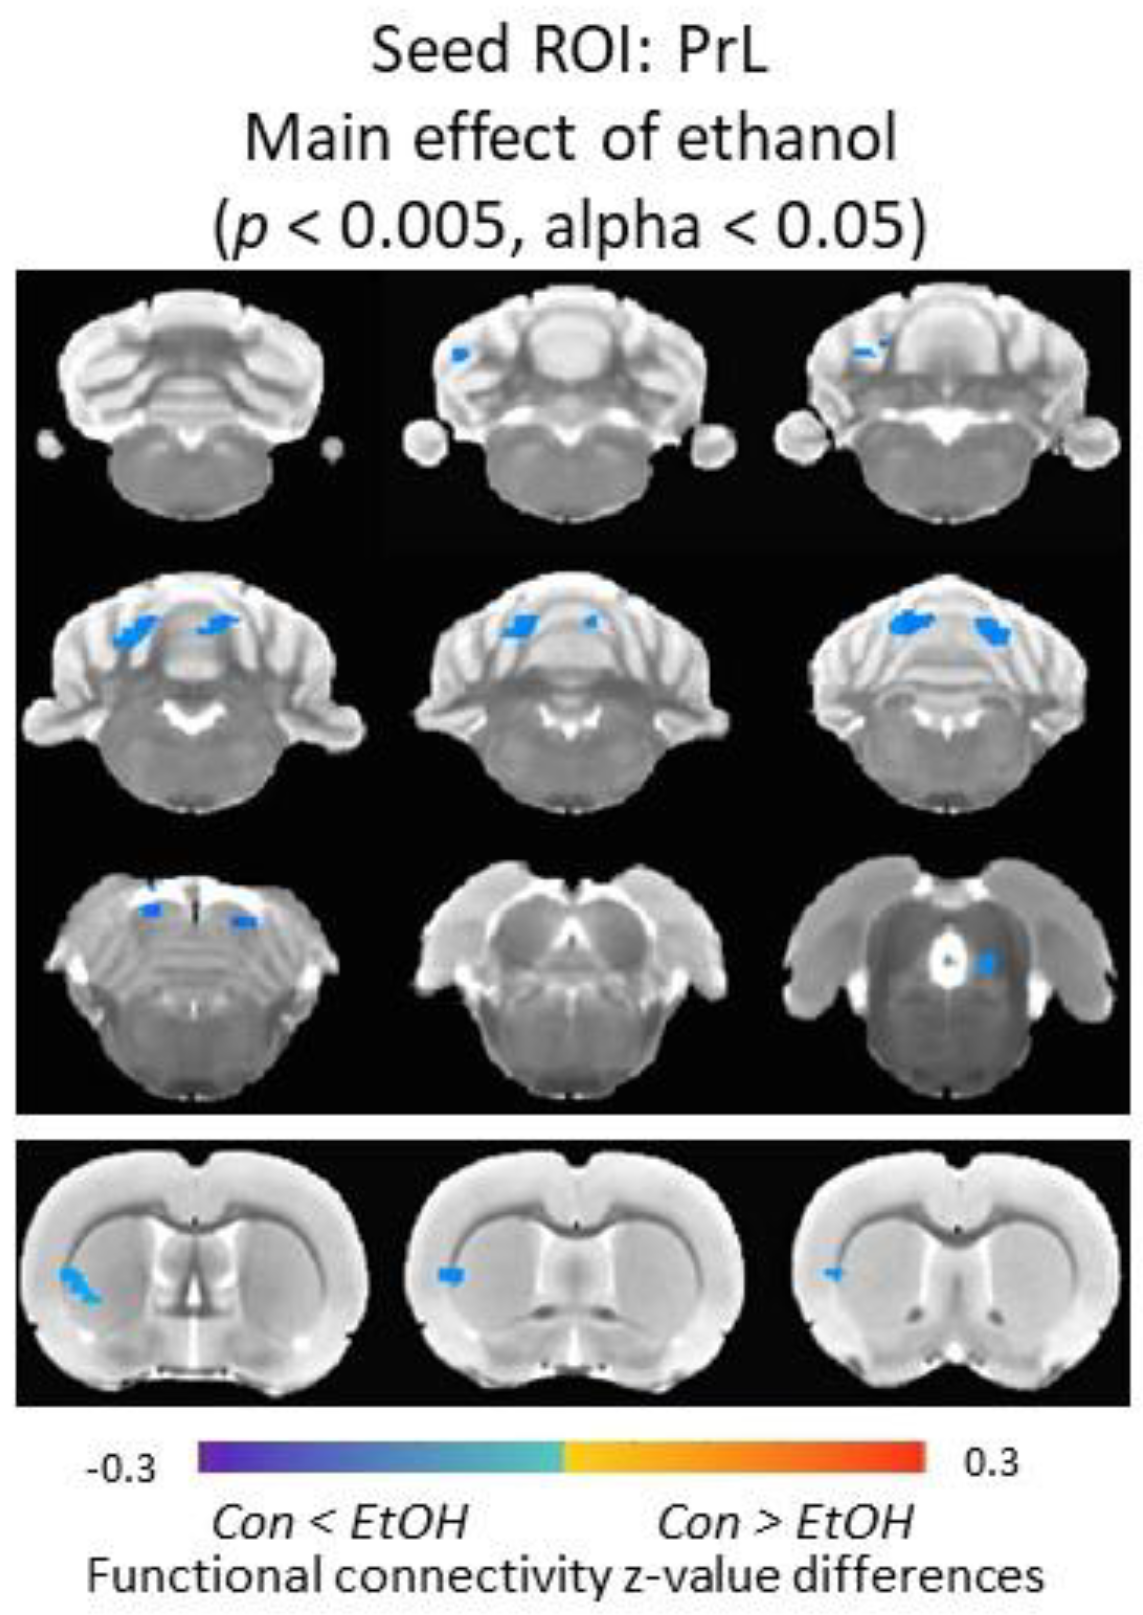

3.6. Functional Connectivity of the Prelimbic Cortex and Cerebellum Was Increased in Ethanol-Exposed Male Rats